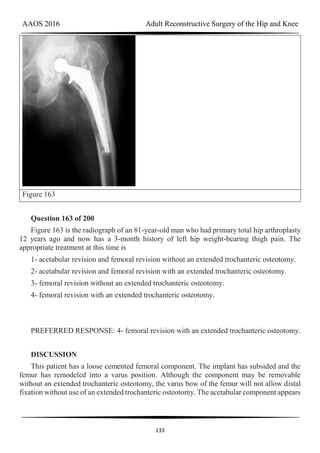

1- Obesity

2- Lateral hinge fracture

3- Smoking

4- An accelerated weight-bearing protocol

PREFERRED RESPONSE: 3- Smoking

AAOS 2016 Adult Reconstructive Surgery of the Hip and Knee

125

DISCUSSION

Many factors can lead to delayed union or nonunion after medial opening-wedge high

tibial osteotomy; the factor most associated with delayed union or nonunion is smoking. Other

factors include obesity and unstable lateral hinge fractures, but to a lesser extent. An

accelerated weight-bearing protocol has no effect on union. The use of locking screws should

increase construct stability and is not associated with osteotomy delayed union or nonunion.